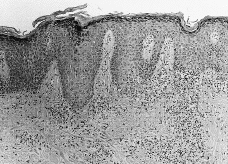

La histología (Figs. 4, 5, 6 y 7) correspondía a un patrón liquenoide en tres de ellos, a una dermatitis espongiótica en otro y una hiperplasia pseudoepiteliomatosa en el restante (tabla II). Realizadas las pruebas epicutáneas, a las pacientes 1 y 2 con la batería estándar del GEIDC, batería de colorantes textiles, mercurio, cadmio y la tinta que ellas aportaron, y al 4 únicamente con su tinta, encontramos una positividad a la tinta la paciente número 2 (++/+++). Hemos realizado 25 controles con dicha tinta, encontrando sólo una positividad, por lo que interpretamos que la reacción de nuestra paciente no es irritativa.

FIG. 6.--Paciente número 4. Epidermis con acantosis, córnea compacta y mínima espongiosis. En la dermis se observa un infiltrado linfocitario perivascular superficial.